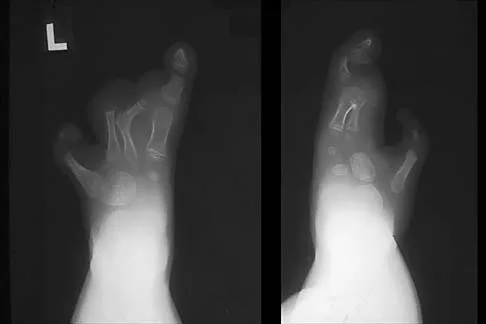

A 45-year-old male karate instructor sustained the injury shown in Figures 40a through 40c while practicing karate. The decision to proceed with surgery depends on which of the following factors?

Explanation

The most important criteria in determining the need for surgery following a nondisplaced or minimally displaced tibial plateau fracture is knee stability to varus/valgus stress. Soft-tissue injury noted on MRI may be addressed at a later time following fracture healing. This fracture pattern is amenable to nonsurgical management. Decisions regarding surgical intervention may be made up to 2 weeks after injury.